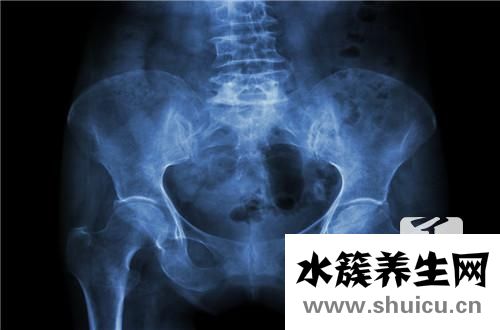

盆腔積液是一種婦科普遍性的癥狀,那麼醫治盆腔積液打消炎藥可以嗎?這一問題要實際問題實際看待。最先,應了解一下什么叫盆腔積液。

盆腔積液為女士骨盆中的液體,其在臨床醫學上被分成生理性的與生理性的兩類。生理性的盆腔積液是女性身體一切正常狀況,大部分女士都多多少少的存有生理性盆腔積液。此外,女性檢查的時間針對盆腔積液的查驗結果也是有所區別的。因此,若是查驗結果超出了10公分這一定義指標值,女士可選別的時間再開展一次查驗。

而若是查驗結果顯著超過10公分,那麼基本上能夠分辨當今人體內存有的盆腔積液為生理性的。醫師強調,生理性的盆腔積液不是需要醫治的。可是,生理性的盆腔積液則需要醫治。生理性的盆腔積液多是由于發炎問題來講引起的,因此醫治上關鍵選用消炎方式 。